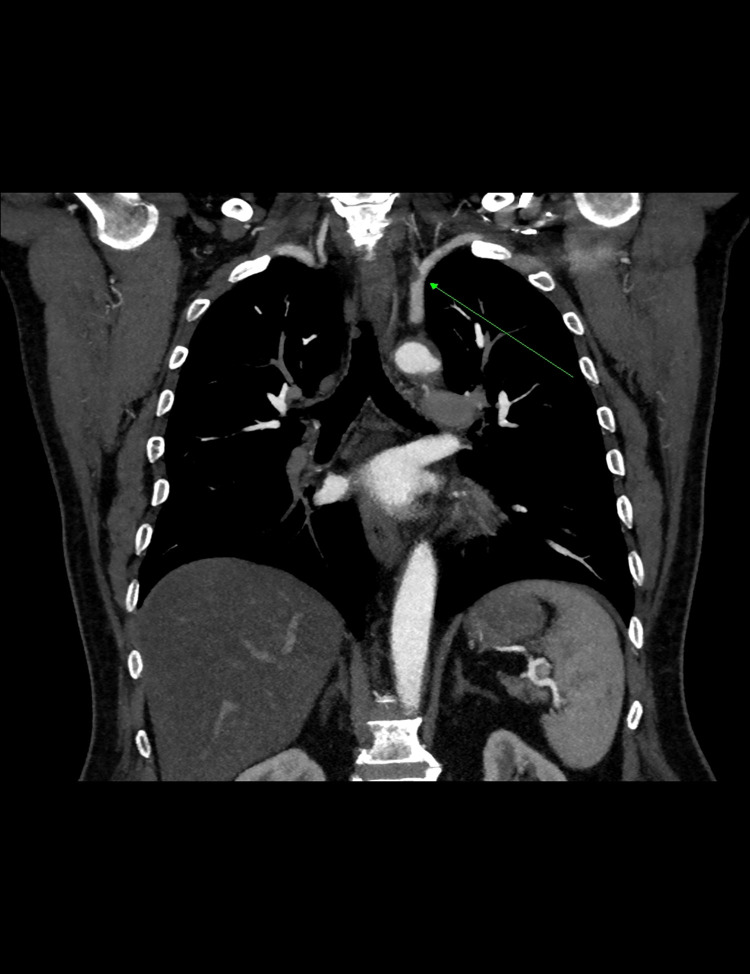

Case presentation: We present a case of incidentally discovered left subclavian stenosis in a 65-year-old male who was admitted for spinal surgery. The patient had a history of peripheral arterial disease, diabetes mellitus, and heavy smoking. During the preoperative assessment, the blood pressure readings in the department were within the normal range. In the operating theater, blood pressure readings of the two arms revealed readings of 136/85 mmHg and 235/114 mmHg in the right and left arms, respectively. Accordingly, the operation was postponed for further evaluation of the increased interarm systolic blood pressure difference. Computed tomography angiography revealed focal stenosis at the origin of the left subclavian artery, causing approximately 90% narrowing. The patient underwent a successful subclavian artery angioplasty.

背景:锁骨下动脉狭窄主要由动脉粥样硬化改变引起,可导致上肢和中枢神经系统发生缺血事件。其他病因包括辐射暴露、血管炎、神经纤维瘤病、外压迫综合征和纤维肌肉发育不良。这些患者的常规麻醉挑战是维持脑灌注。病例介绍:我们报告一例偶然发现左锁骨下狭窄的65岁男性谁是入院脊柱手术。患者有外周动脉疾病、糖尿病和重度吸烟史。术前评估时,科室血压读数在正常范围内。在手术室中,两臂的血压读数显示右臂和左臂分别为136/85 mmHg和235/114 mmHg。因此,手术被推迟,以进一步评估臂间收缩压差的增加。计算机断层血管造影显示左侧锁骨下动脉起源处局灶性狭窄,导致约90%狭窄。患者接受了成功的锁骨下动脉血管成形术。结论:报告有外周动脉疾病、重度吸烟或严重代谢综合征病史的患者的血压读数是很重要的。锁骨下狭窄患者容易出现臂间收缩压差增高。因此,双侧血压测量是一种简单的测试,在紧急情况下对麻醉前评估有重要影响。